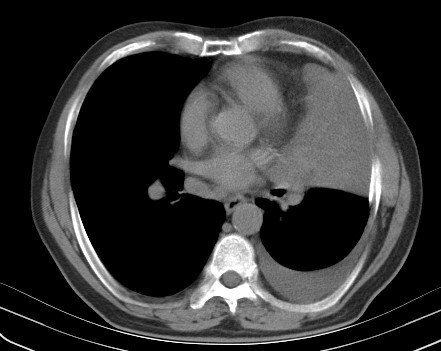

以下是引用老爱克斯新网客在2008-7-31 6:30:00的发言:[br]左肺上叶大片状病灶,左肺上叶支气管狭窄呈鼠尾状,左肺门增大,纵隔内见肿大淋巴结,左侧胸腔积液,余肺清晰。左肺中心型肺癌淋巴结转移,

以下是引用zjzjr在2008-7-31 8:45:00的发言:[br]考虑左侧中心性肺癌伴阻塞性肺炎,左肺上叶肺不张,纵隔淋巴结转移;左侧胸腔积液。建议行纤支镜检查。

以下是引用zjb在2008-7-31 6:32:00的发言:[br]左侧中心性肺癌 阻塞性肺炎 肺不张 胸腔积液 建议气管镜

以下是引用sdzyy在2008-7-31 8:47:00的发言:[br]病灶较治疗前有所进展,胸水增多, 左侧中心性肺癌 并 阻塞性肺炎 肺不张 胸腔积液 可能性大; 建议气管镜检查。 [br] [br]